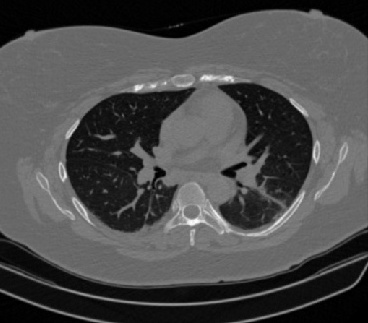

Figure 1 shows four CT scan slices, two from a non-COVID-19 CT scan, on the left and two from a COVID-19 scan, on the right. Bilateral ground glass regions are seen especially in lower lung lobes in the COVID-19 slices.